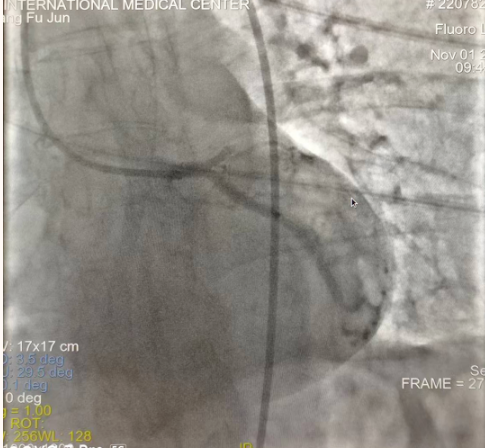

閉塞的血管再通時間取決于急救時長、轉(zhuǎn)運時長和治療時長,在前兩方面,醫(yī)院已為患者爭取了最短時間?;颊呒覍龠h在陜北,雖然已在趕來的路上,但最快抵達西安也要3小時,在與患者家屬電話溝通同意急診手術后,醫(yī)療總值班代家屬簽字,康曉軍在請示心臟病醫(yī)院王海昌院長及心臟內(nèi)科CCU尚福軍主任后,積極進行術前準備。在沒有家屬陪同、沒有交費、沒有辦入院手續(xù)的情況下,患者經(jīng)胸痛中心綠色通道被送往心臟冠脈介入手術室,打通了完全閉塞的心臟前降支近段血管。